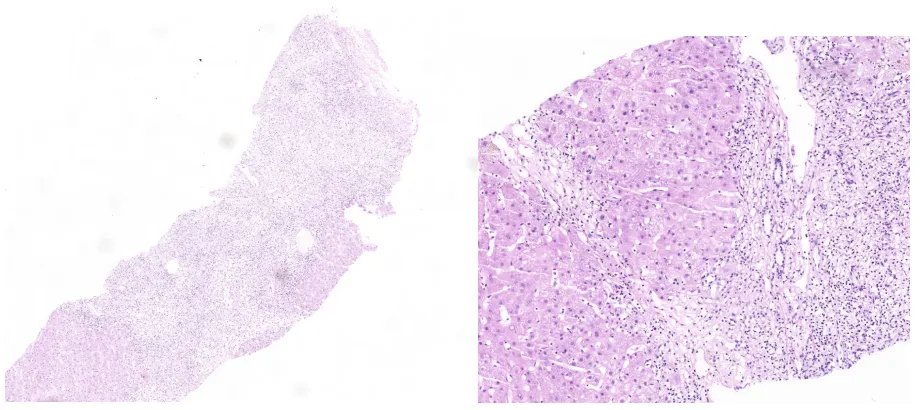

肝脏病理:肝小叶结构中-重度紊乱,局灶形成假小叶,小叶内肝细胞浊肿、变性及多个碎片状及融合性坏死,中度界板炎,汇管区-汇管区及汇管区-中央静脉之间融合性坏死及纤维化。